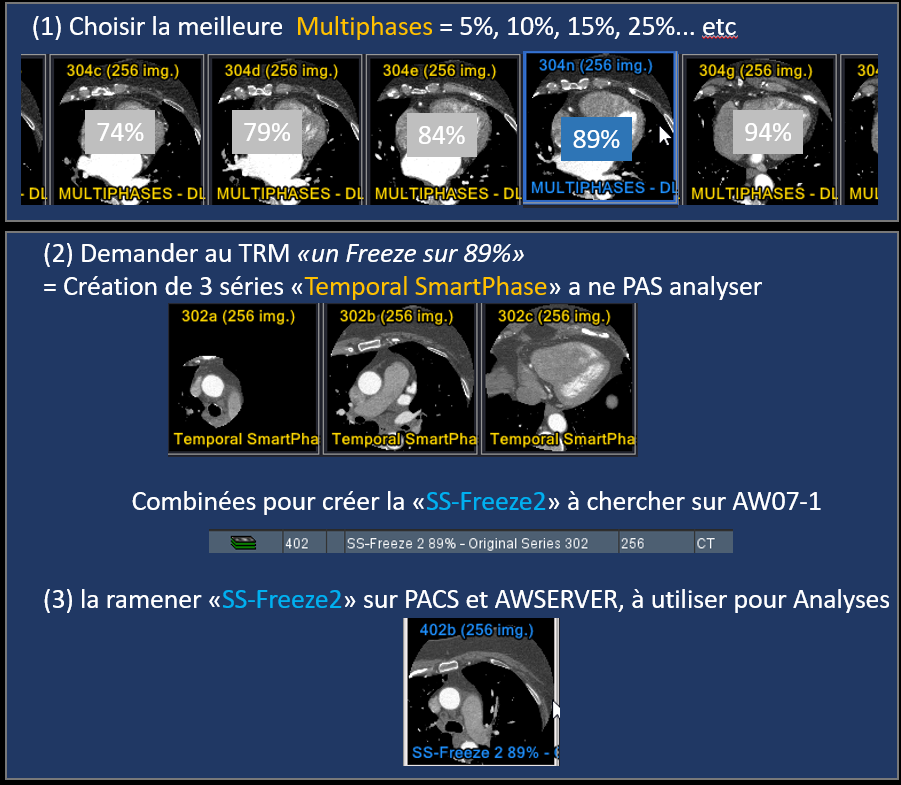

- Temporal SmartPhase = fais 3 séries, envoyer depuis le AW la SS-Freeze qui combine les trois, standard a 75%, mais la machine peut en trouver un ou ca bouge moins

- Toujours reconstruire les multiphases, ca peut être utile pour le futur

Reconstructions SS-Freeze